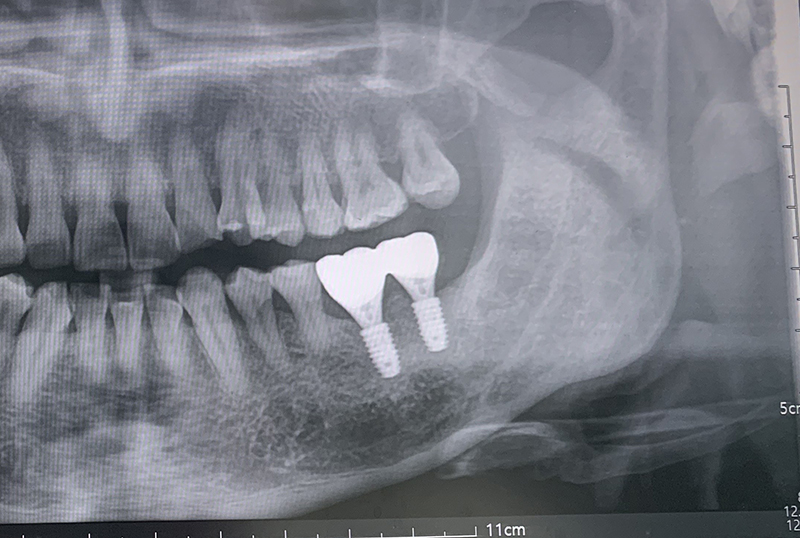

그리고 내 기억에 6개월에서 1년 사이 정도 지나 잇몸뼈가 다시 생긴 후에 임플란트를 했다. 나의 경우 빼고 바로 뼈이식을 하지 않고 치조골이 생긴 후에 임플란트를 했다.(6개월 정도만 지나면 잇몸뼈가 생긴다고 했다.) 잇몸치료에 비해 이건 아픈 것 하나도 없다. 이미 치조골이 녹고 있다면 회복 불가하니 나처럼 고생하지 말고 그냥 바로 빼고 기다렸다가 임플란트 하는 게 제일 낫다고 본다.